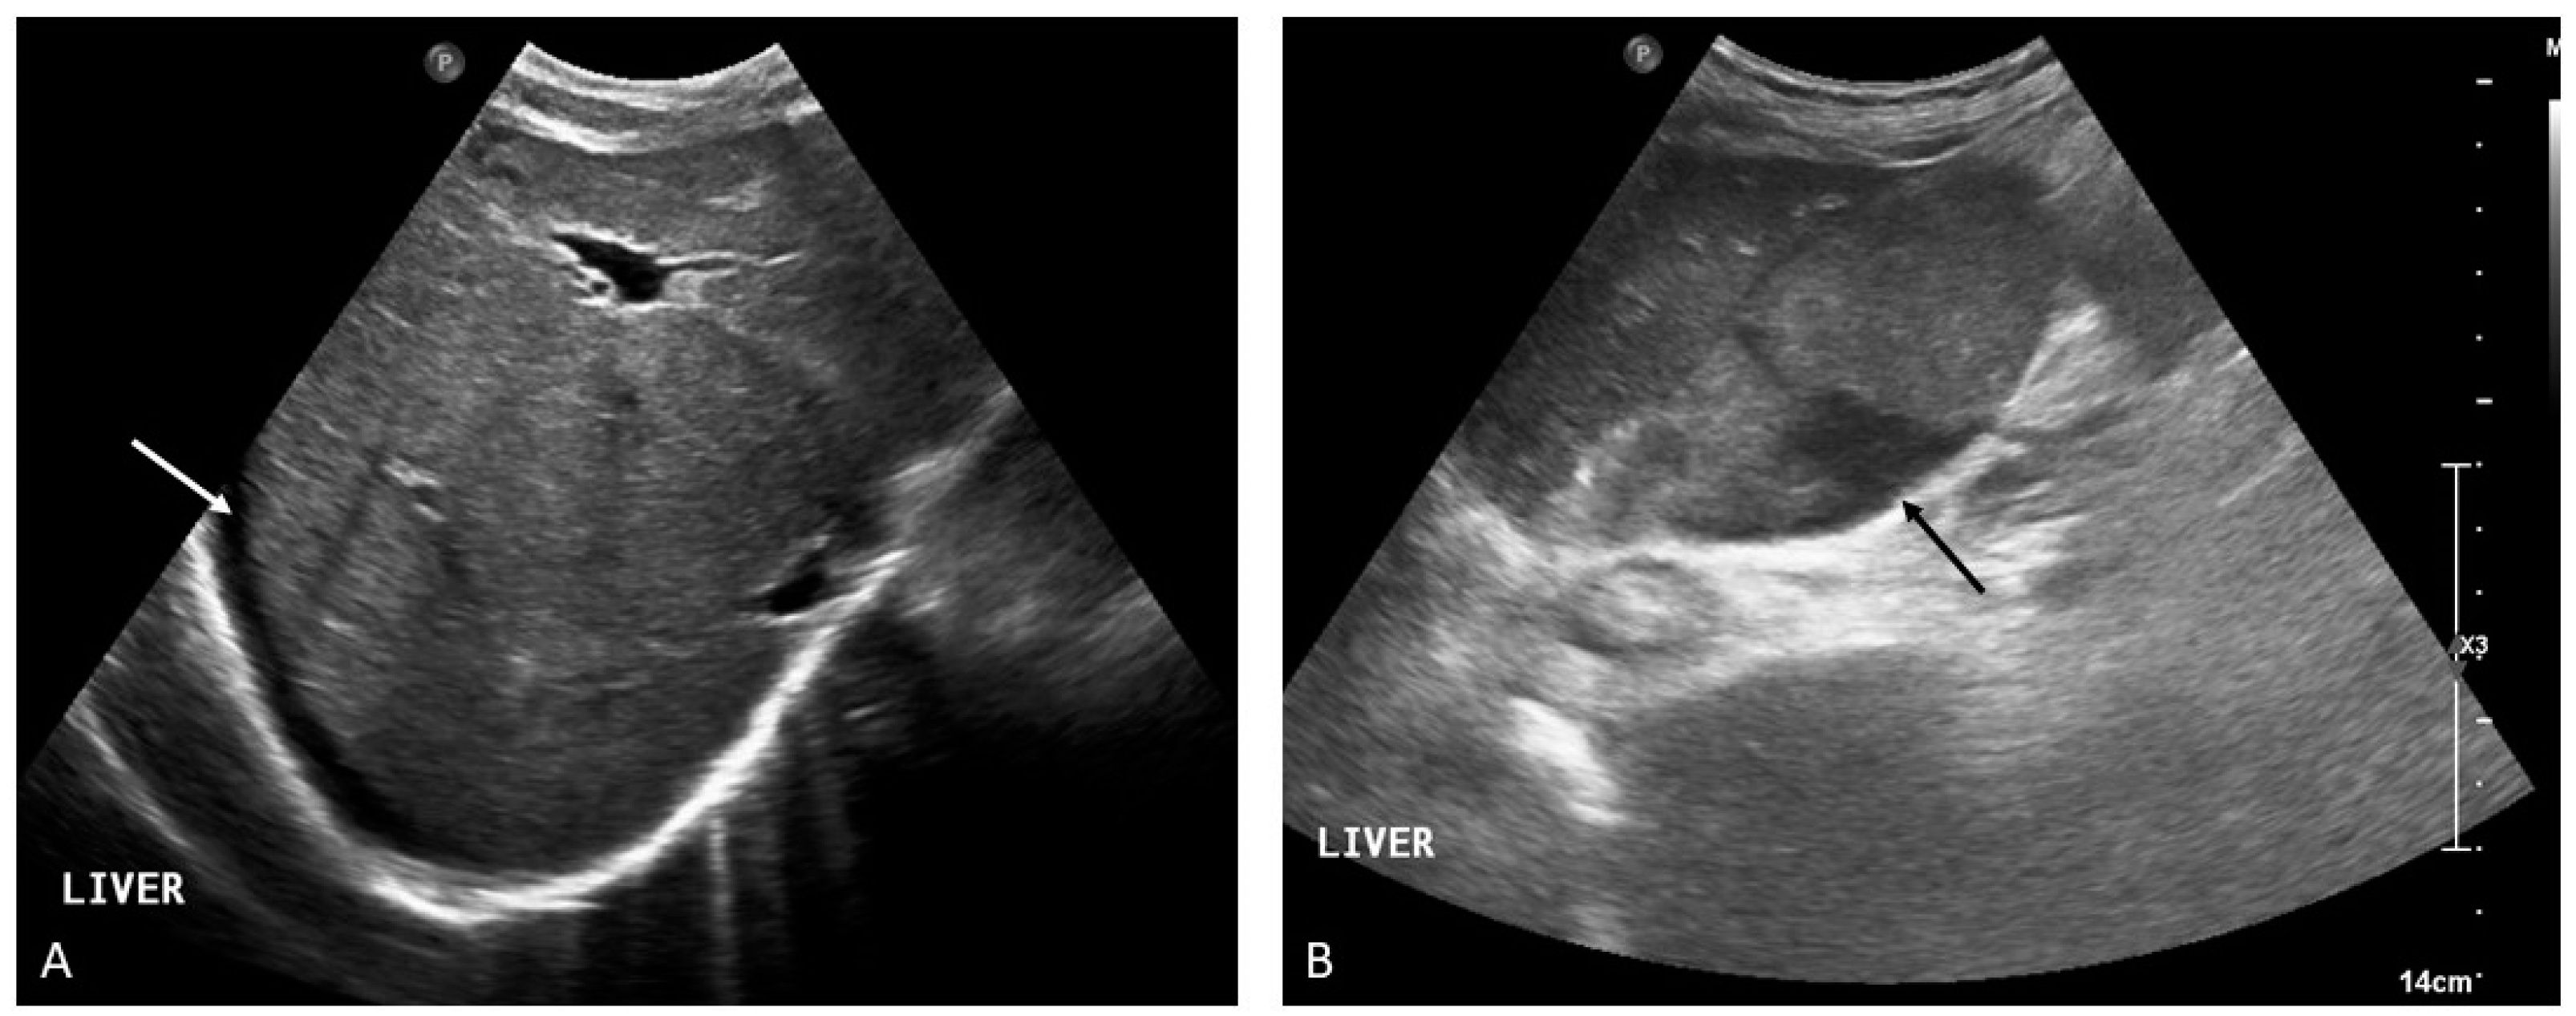

2. Portal Vein Thrombosis

- (i)

- the presence of primary or secondary liver malignancy and echogenic material filling the portal venous lumen;

- (ii)

- the diameter of the lumen of the portal vein is often increased according to the growth of the tumor within the vessel;

- (iii)

- evidence of vascularization of the thrombus as a consequence of neoplastic neoangiogenesis [1].